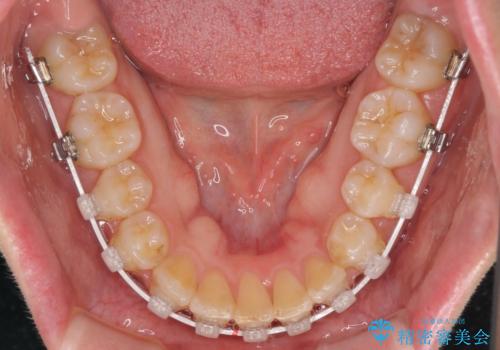

- 右上の八重歯と、左下八重歯を抜いてしまったことを気にして来院された患者様です。

下顎は既に犬歯を1本抜歯しているため、上顎右側第一小臼歯を抜歯し、ワイヤー装置にて歯列を整えることとしました。

変則的な抜歯となるため、正中と人中がずれる可能性がありましたが、仕上がりは上下正中を揃えることができました。